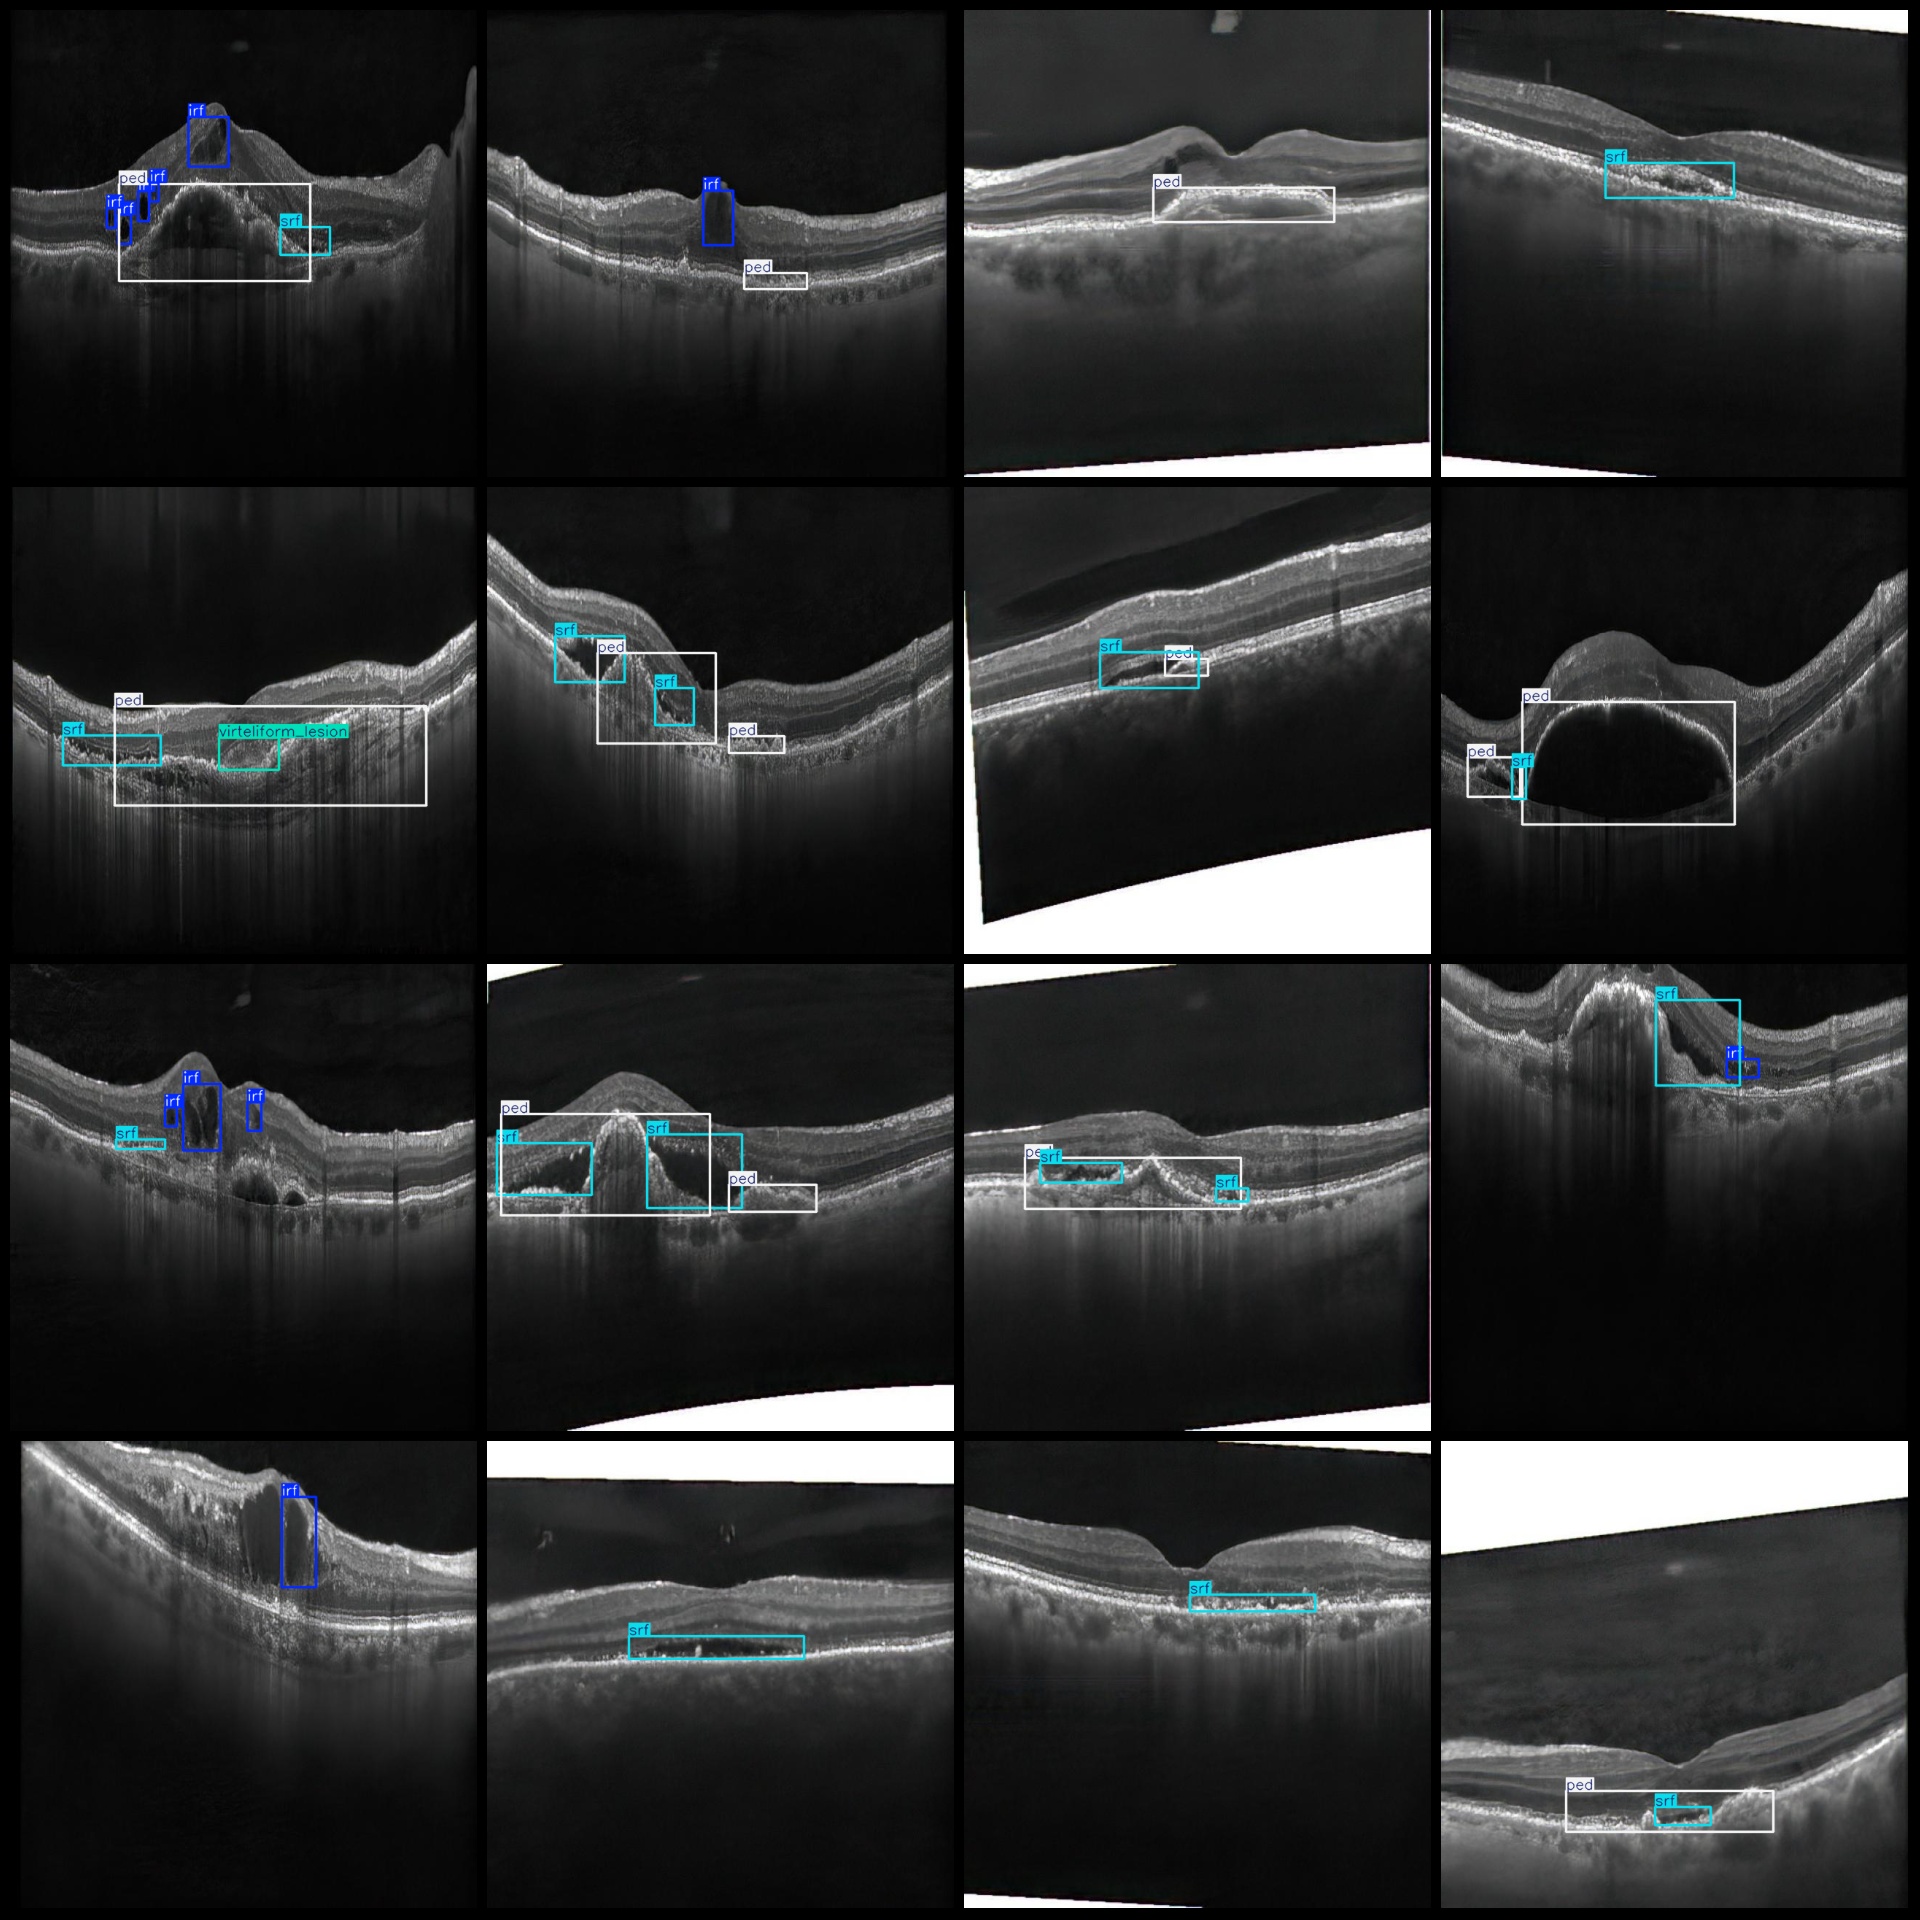

图片预览:

标注例子:

标注类别名称(注意yolo格式类别顺序不和这个对应,而以labels文件夹classes.txt为准):["irf","organized_subretinal_scar","ped","srf","subretinal_hyperreflective_material","virteliform_lesion"]

irf(视网膜内高反射点) 框数 = 4878

organized_subretinal_scar(组织化视网膜下瘢痕) 框数 = 326

ped(色素上皮脱离) 框数 = 3611

srf(视网膜下液) 框数 = 3794

subretinal_hyperreflective_material(视网膜下高反射物质) 框数 = 91

virteliform_lesion(玻璃膜疣样病变) 框数 = 194